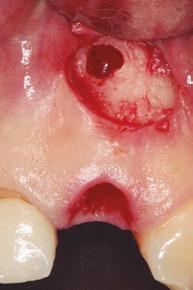

–Implante inmediato en incisivo lateral superior con técnica de «Socket Shield» y acceso vestibular para legrado de la lesión periapical, por el Dr. Ignacio Tormo Jiménez y cols. [106]